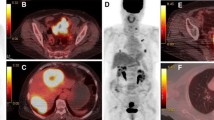

There was no statistical significance in clinicopathological features in gender, age, primary tumor site, tumor length, pathological grade, clinical tumor stage, lymph node metastasis, distant metastasis site, CEA, and CA-199 between the KRAS mutant patients and the KRAS wild-type patients. In the PET traditional parameters, SUVmax (19.00 vs. 13.16, p < 0.001) (Fig. 2a), MTV (11.64 vs. 8.83, p = 0.001) (Fig. 2b), and TLG (102.85 vs. 69.76, p < 0.001) (Fig. 2c) in the KRAS mutant group were significantly higher than those in the KRAS wild-type group. Heterogeneity parameters CV2.5 (0.55 vs. 0.46, p = 0.006) (Fig. 2d) and HI-2 (14.03 vs. 7.59, p < 0.001) (Fig. 2e) in the KRAS mutant group were significantly higher than those in the wild group, while CV40% (0.22 vs. 0.24, p = 0.001) (Fig. 2f) was significantly lower than that in the wild group. There was no significant difference in HI-1(p = 0.177) (Fig. 2g) between the two groups (detail in Table 2).

Predictive value

The ROC curve and area under the curve (AUC) were used to infer the potential predictive value of PET parameters on KRAS mutation status. The optimum threshold of SUVmax was 17.24 (AUC = 0.722), with sensitivity and specificity of 63.4% and 76.7% in predicting KRAS mutant (Fig. 3a). With a point of 7.62, the AUC of MTV was 0.695. MTV showed higher sensitivity of 90.2% but lower specificity of 45.0% (Fig. 3b). Using a cut-off of 68.66, the AUC of TLG was 0.749 with a sensitivity of 94.9% and specificity of 50.0% (Fig. 3c). The optimum cut-off value of CV2.5 was 0.51 (AUC = 0.661), the sensitivity was 63.4%, and the specificity was 73.3% (Fig. 3d). The AUC of HI-2 was 0.746, the sensitivity was 73.2%, and the specificity was 66.7% when using a threshold of 9.95 in predicting KRAS mutant (Fig. 3e).

With a cut-off of 0.24, the AUC of CV40% was 0.694 with a sensitivity of 73.2% and specificity of 60.0% in predicting KRAS WT (Fig. 3f).